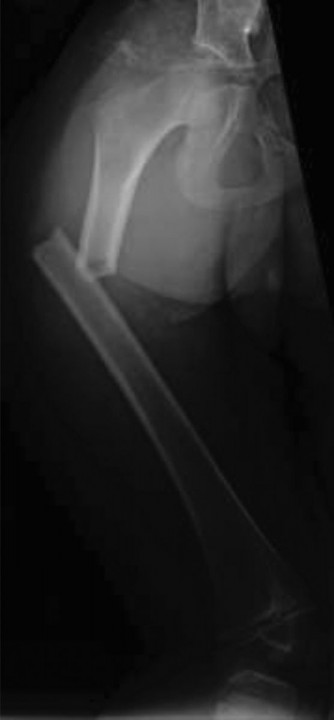

CASE 4 An 11-year-old girl was transferred from an outside hospital for furthe…